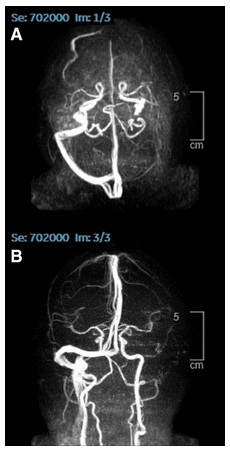

Sinusvenenthrombose

Sinusvenenthrombose 2 Röntgenfotos

Sinusvenenthrombose 2 Röntgenfotos [3]

Ein 80jähriger Mann wird in der Notaufnahme eines Krankenhauses vorstellig. Er leidet seit 2 Wochen unter schweren Kopfschmerzen, die mit Tinnitus und Sehstörungen einhergehen. Die Symptome haben sich einen Tag nach seiner ersten Behandlung mit der Gentherapie BNT162b2/Comirnaty von Pfizer/Biontech eingestellt. Schmerzmittel brachten keine Linderung, im Gegenteil, die Symptome wurden ergänzt durch psychologische Qual, Konzentrationsschwierigkeiten und Schlafstörung. Bei Aufnahme hatte der Mann einen erhöhten Blutdruck. Eine nähere Untersuchung ergab zudem eine Einschränkung seiner Sehfähigkeit, Schwäche in allen vier Gliedern und reduzierte Reflexe. Eine Kernspintomographie zeigt einen vollständig fehlenden Blutfluss in der transversen Sinusvenene und der linken Drosselvene, im Einklang mit der Diagnose einer zerebralen Sinusvenentrombose. Durch die sofort eingeleitete Behandlung mit Apixaban trat eine Besserung des Zustands des Mannes ein. Er konnte nach drei Monaten entlassen werden. Die Nachbehandlung dauerte bei Schriftlegung des Beitrags noch an.

Qureshi, Muhammad Imran Ahmad, Bilal Azam, Muhammad Aamir Waheed, and Afsheen Imran (2022). Venous sinus thrombosis after the first dose of Pfizer BioNTech vaccine. BMJ Case Reports CP 15(5): e247493.